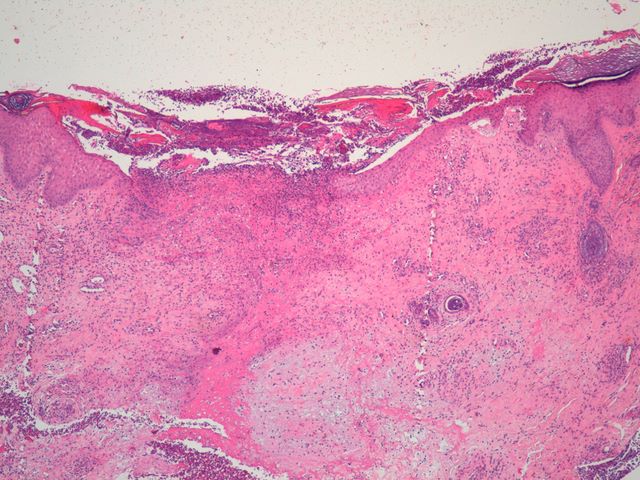

1090 -- 002.jpg